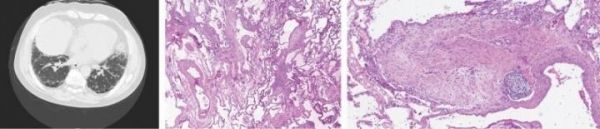

Image: Images show, from left, a chest CT scan of a patient with idiopathic pulmonary fibrosis and lung biopsies displaying the typical disease pattern and scarring. (Credit: Cedars-Sinai)